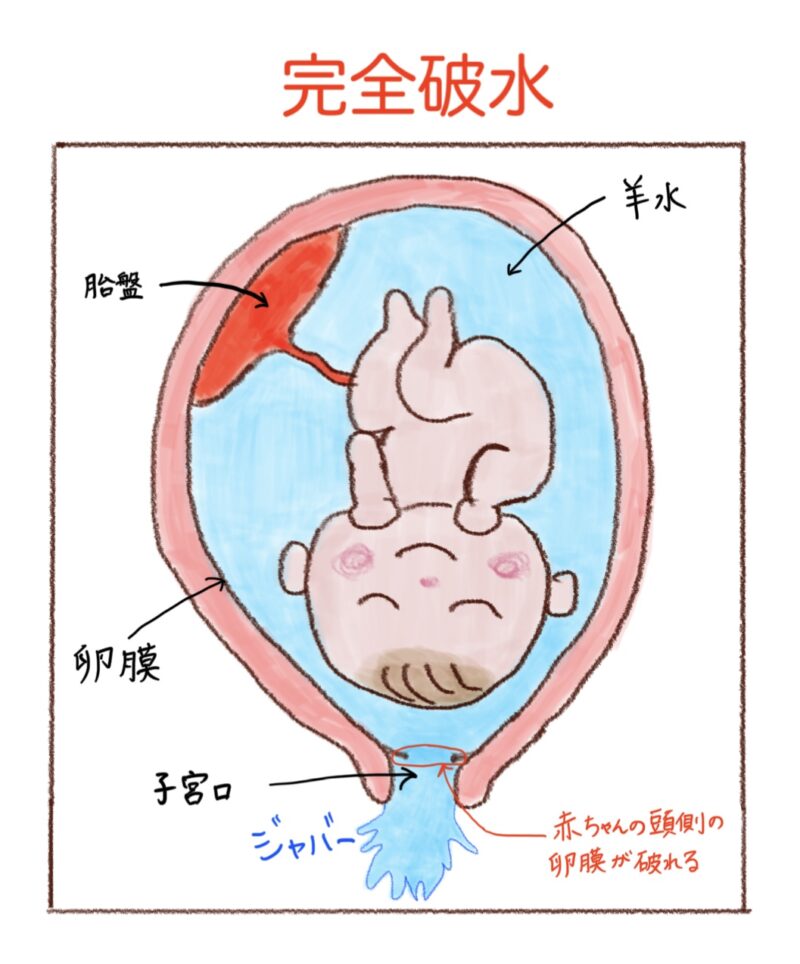

破水

破水とは、赤ちゃんを包んでいる膜(卵膜)が破れて羊水が出てくることです。

ちなみに、破水には2種類あって、

一つ目は、「完全破水」といって、赤ちゃんの頭側の卵膜が破れる事で、よく「パンっと何かがはじけたような感じがする」と言われます。

自分の意思とは関係なく比較的たくさんの量の羊水がダラダラと出てくるのが特徴です。